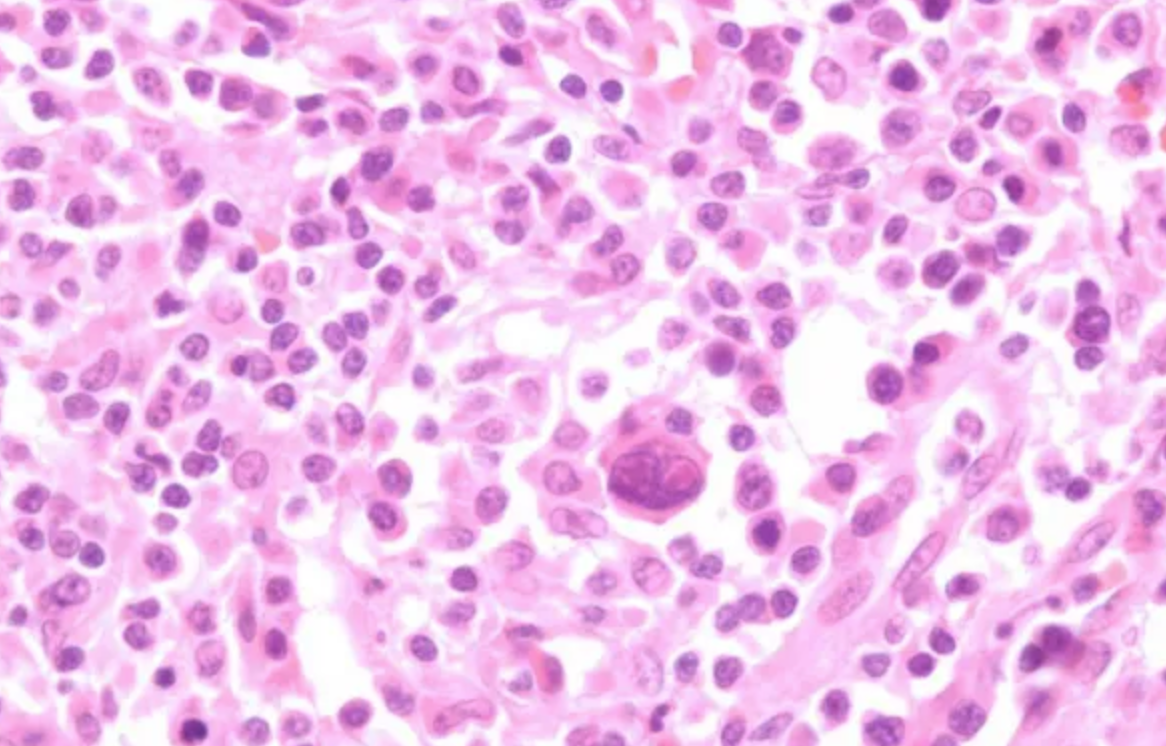

• Reed-Sternberg cell: 특징적인 모양의 거대 종양 세포

• 배경에 다양한 염증 세포 침윤